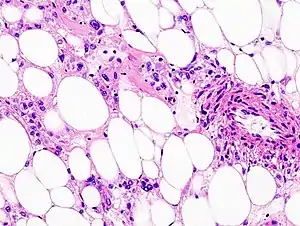

Histopathologic image of renal angiomyolipoma. Nephrectomy specimen. H&E stain.

PECs consist of perivascular epithelioid cells with a clear/granular cytoplasm and central round nucleus without prominent nucleoli.

PECs typically stain for melanocytic markers (HMB-45, Melan A (Mart 1), Mitf) and myogenic markers (actin, myosin, calponin).